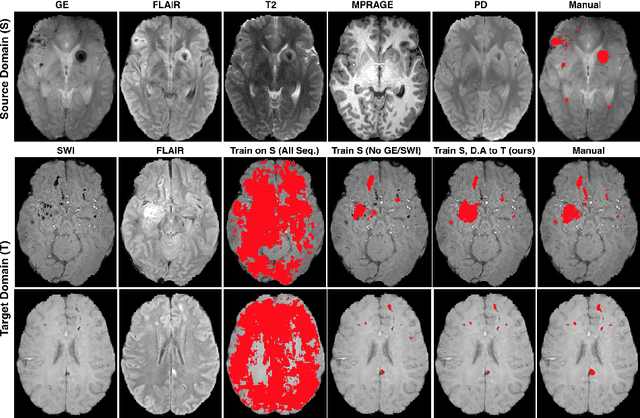

Abstract:Significant advances have been made towards building accurate automatic segmentation systems for a variety of biomedical applications using machine learning. However, the performance of these systems often degrades when they are applied on new data that differ from the training data, for example, due to variations in imaging protocols. Manually annotating new data for each test domain is not a feasible solution. In this work we investigate unsupervised domain adaptation using adversarial neural networks to train a segmentation method which is more invariant to differences in the input data, and which does not require any annotations on the test domain. Specifically, we learn domain-invariant features by learning to counter an adversarial network, which attempts to classify the domain of the input data by observing the activations of the segmentation network. Furthermore, we propose a multi-connected domain discriminator for improved adversarial training. Our system is evaluated using two MR databases of subjects with traumatic brain injuries, acquired using different scanners and imaging protocols. Using our unsupervised approach, we obtain segmentation accuracies which are close to the upper bound of supervised domain adaptation.